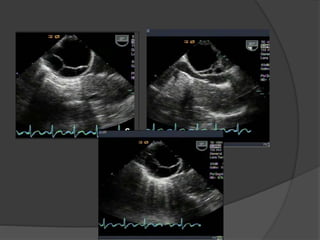

Follow-up US

Case 2: 12 year old female with abdominal pain

Dilated fallopian tube with thickened and enhancing tubal wall

Right

ovary

Complex

tubular

mass

Normal left ovaryNormal left ovary flow

Diagnosis: Torsion of the left Fallopian tube

Dilated tube with thickened, echogenic walls

and absence of vascular flow in the tube

Isolated torsion of the fallopian

tube

 Rare cause of lower quadrant pain primarily affecting